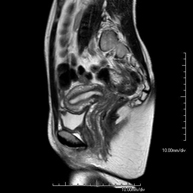

- RM Pelvis femenina

Prueba diagnóstica no invasiva que consiste en la obtención de imágenes de alta definición anatómica de la pelvis mediante el empleo de un campo electromagnético y ondas de radio (con un emisor y un receptor). No utiliza radiación ionizante. Se realiza para estudiar patologías del útero, del ovario, de las trompas y la vagina, ya sean de origen tumoral, inflamatorio o vasculares. Además permite valorar les estructuras adyacentes localizadas en la pelvis, identificando sus alteraciones. A veces requiere el uso de contraste intravenoso (Gadolinio) para caracterizar las lesiones.